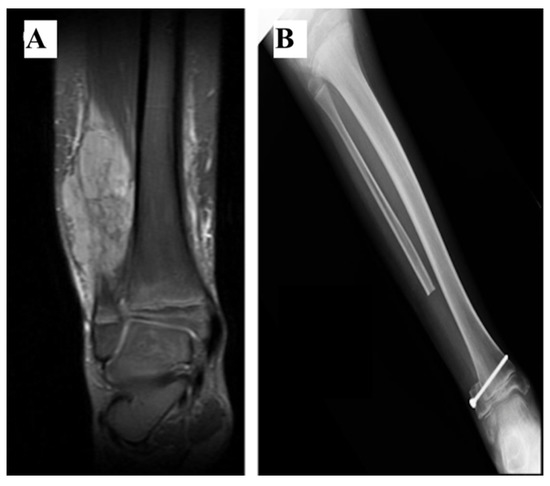

2.5. No Reconstruction

| 8 | 115 | 17.8 | No | No | No | Yes | 3 | No | - | Peroneal nerve palsy Chronic pain | No | 27 |

| 9 | 120 | 18 | Yes | No | No | No | 3 | No | - | - | No | - |